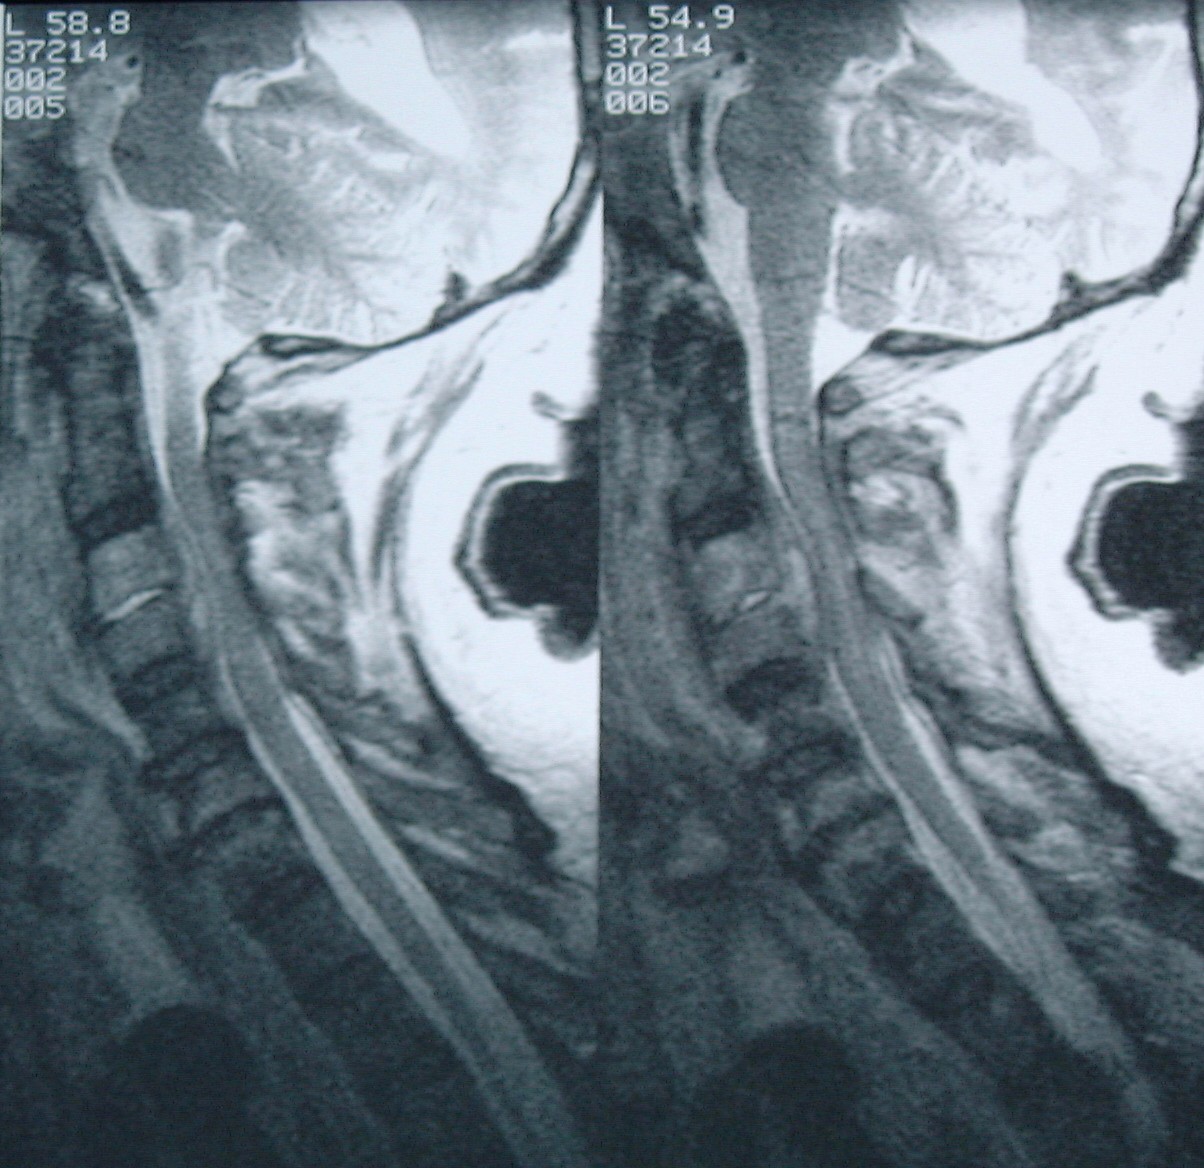

Si chiama EpCS, ovvero una bilaterale epidurale prefrontale stimolazione corticale, ed è un metodo di stimolazione elettrica cerebrale dei poli anteriori frontali e della corteccia prefrontale laterale.

«La stimolazione corticale ha diversi vantaggi, a condizione che mostri la sua efficacia nel trattamento della depressione. È reversibile, non è distruttiva e potenzialmente più sicura rispetto ad altre forme di stimolazione cerebrale invasiva in quanto le pale stimolanti non entrano in contatto diretto con il cervello» ha poi aggiunto Nahas.